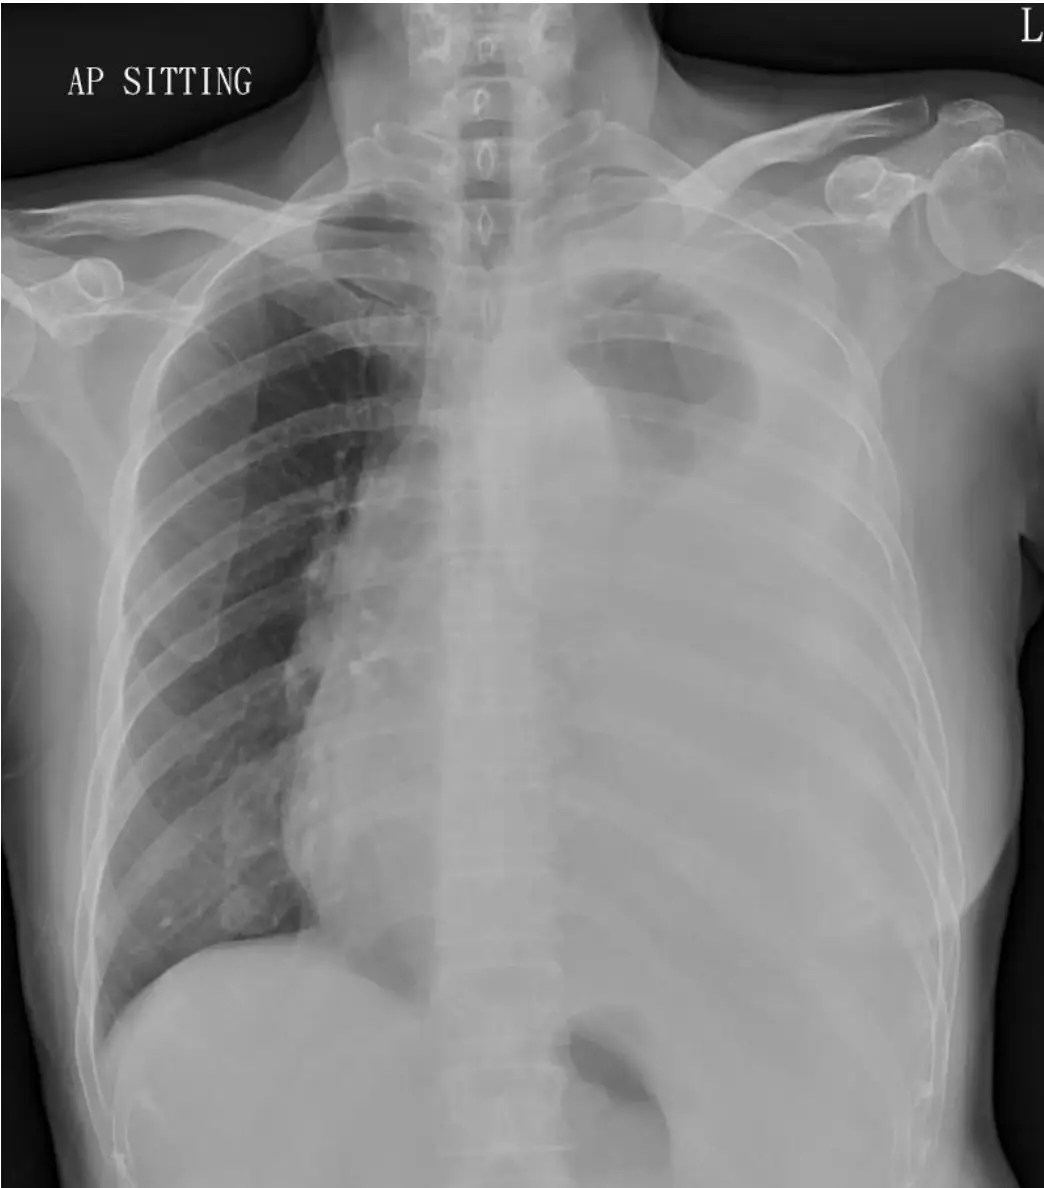

林女士65歲,無糖尿病病史,因為呼吸急促至急診就醫,胸部X光如圖所示,經胸腔穿刺 (Thoracentesis)抽取肋膜積液緩解症狀,肋膜積液檢驗顯示:RBC 4000/uL, Total nucleated cells 340/uL, lymphocyte predominant, total protein 4.9 g/dL, LDH 254 U/L (normal range 140~271 U/L), Glucose 100 mg/dL, 造成林女士的肋膜積液的原因最不可能為下列何者? 圖片描述

胸部正面坐位(AP sitting)X 光片顯示左側半胸腔廣泛不透光,邊緣呈現積液弧形鐮狀(meniscus sign),左側肋膈角銳利消失,並可能有輕度心肺中線(mediastinum)向右移位現象,符合大量左側肋膜積液影像表現。

林女士胸部X光明顯顯示左側大量滲出性積液,胸腔穿刺後液體符合 Light's criteria 中的滲出性特徵:total protein 4.9 g/dL(高於轉移性閾值)、LDH 254 U/L(接近上限但仍屬滲出性判準),細胞差異以淋巴球佔優勢,glucose 正常。常見淋巴球主導的滲出液病因包含惡性腫瘤(肺癌、mesothelioma、淋巴癌)及結核性胸膜炎。膿胸則典型呈現中性球優勢、低pH/低glucose、高LDH 的化膿性表現,與本例實驗數值完全不符,故選項E 為最不可能原因。